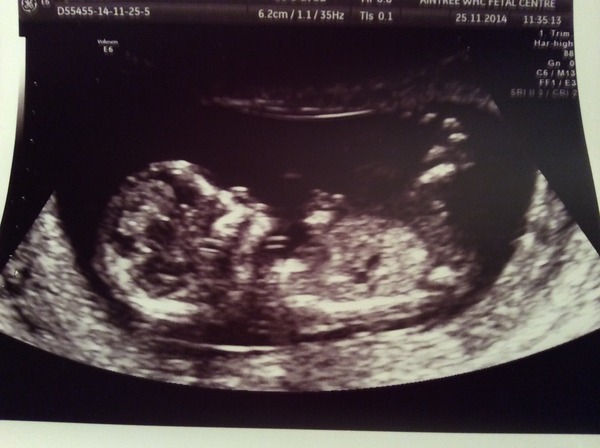

Bellejessleo · 12/12/2014 18:33

Here it is! I love it's little legs, they look so baby like already!